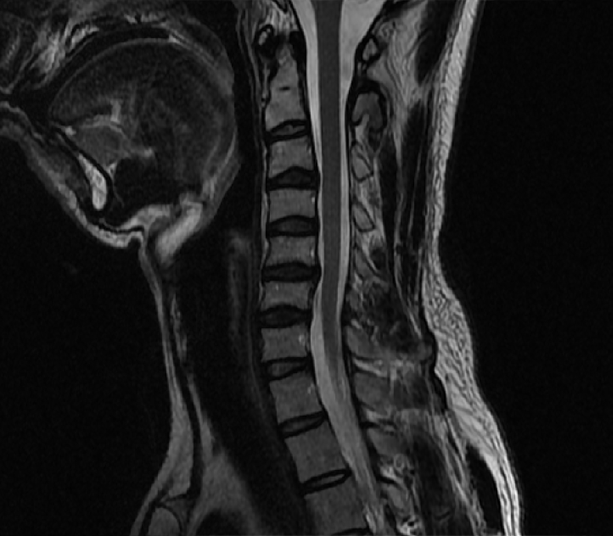

통증은 잠시 줄어들어도 금세 되돌아오는 패턴이 반복됐고, 가장 신경 쓰였던 건 경추 C커브가 무너진 일자목 상태였습니다.

2년 전 찍어둔 경추 엑스레이를 다시 보니 목뼈가 완전히 앞으로 빠져 있더군요.

그동안 통증만 잡으려 했지, 정작 구조적인 회복에는 집중하지 않았다는 걸 그때 깨달았습니다.